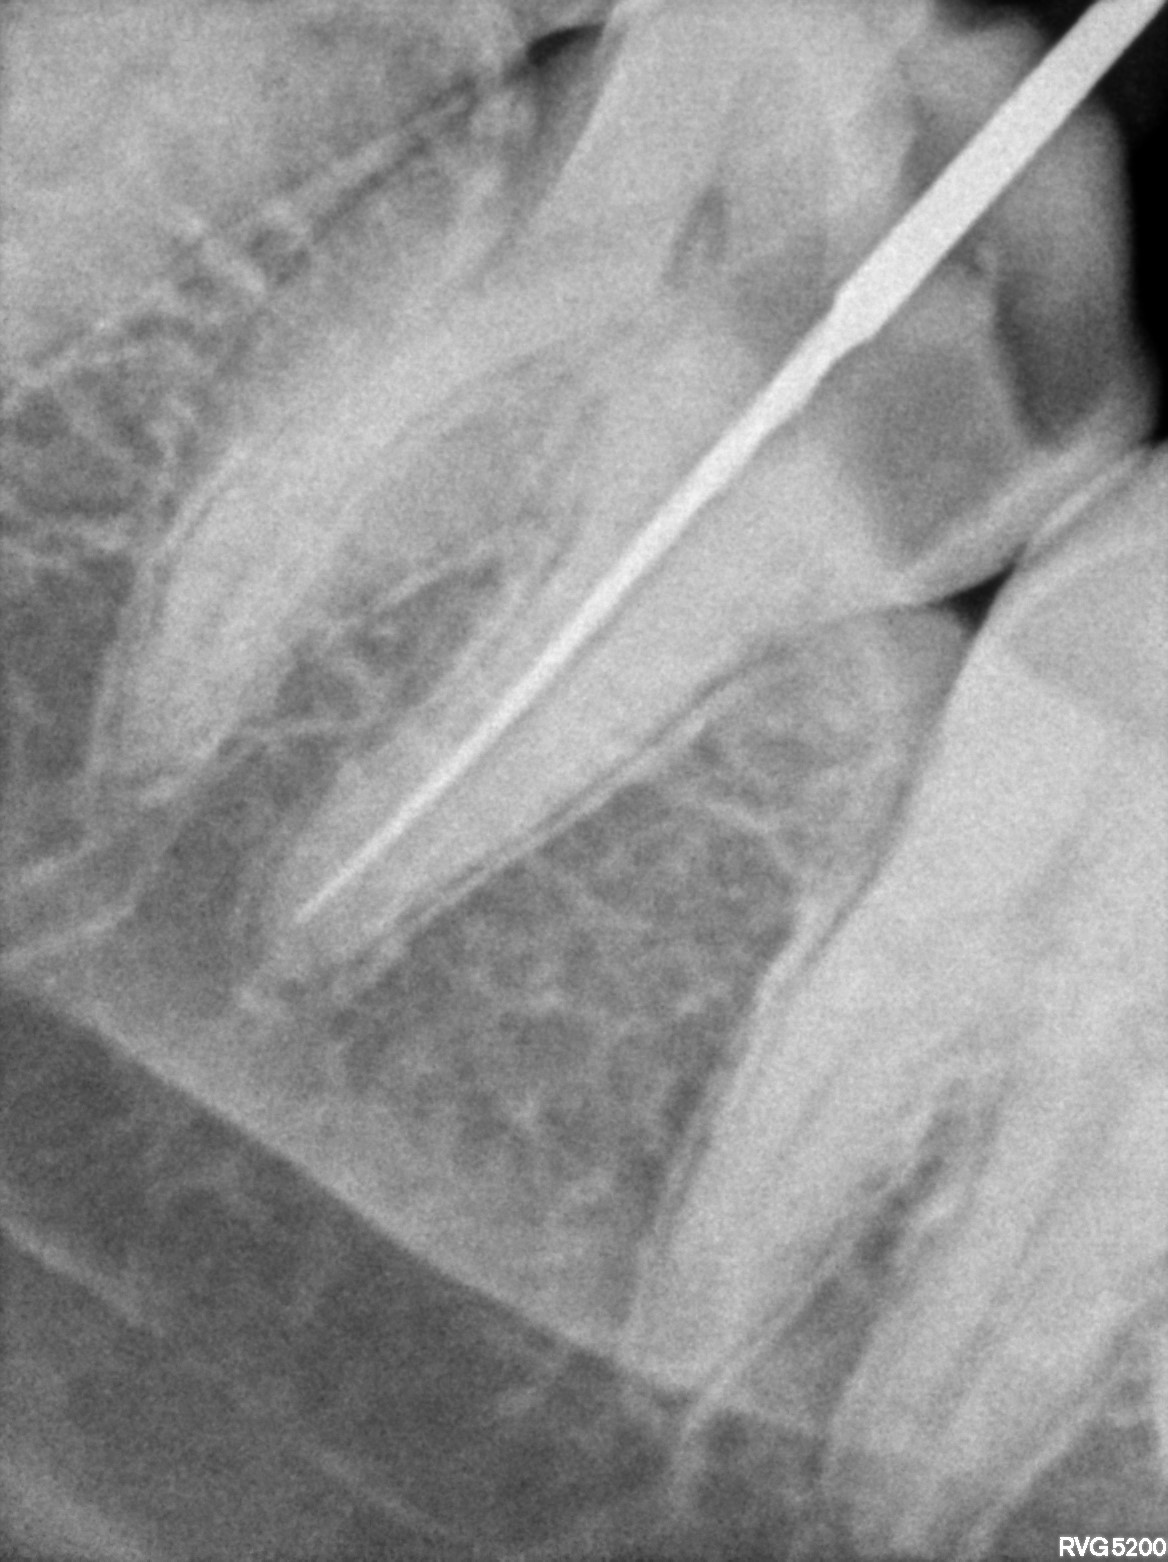

Dental Radiographs FHIR: DocumentReference · LOINC 24641-7

xray_1772613109_4.jpg

24641-7